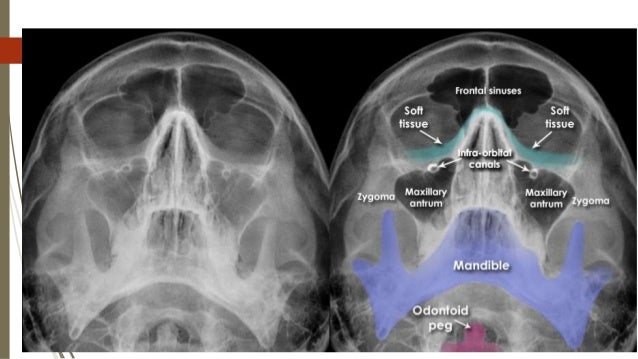

Basic Anatomy Views -importance And Positioning Interpretation Skull

Basic anatomy Views -importance and positioning Interpretation Skull www.slideshare.net

Imaging Of Facial Trauma Part 1

Imaging Of Facial Trauma Part 1 www.slideshare.net

sinus maxillary